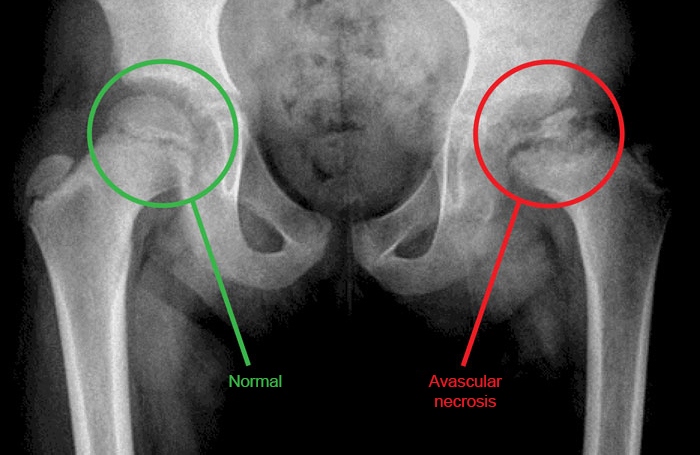

LCP

Legg-Calvé-Perthes disease

Pathogenesis

Idiopathic avascular necrosis of the femur

Clinicalfeatures

Boys age 3-12 Insidious hip pain, limp Restricted hip abduction, internal rotation Positive Trendelenburg sign

Diagnosis

X-ray Early stages: May be normal Later stages: Femoral head flattening, fragmentation, sclerosis MRI: Avascular/necrotic femoral head

Treatment

Non–weight bearing Splinting, possible surgical repair

This patient most likely has Legg-Calvé-Perthes disease (LCP), or idiopathic osteonecrosis (avascular necrosis) of the femoral head. LCP classically affects boys age 3-12, with peak incidence at age 6.

Patients typically have an antalgic gait (avoids weight bearing on the affected side due to pain) and dull, chronic lower extremity pain of insidious onset. The pain may affect the hip directly or present as referred thigh or knee pain, as in this patient. Diagnosis requires a high index of suspicion as initial x-rays may be normal. Persistent symptoms should prompt repeat imaging, which in later stages typically shows sclerosis of the femoral head with flattening and fragmentation. As the disease progresses, examination may reveal limited internal rotation and abduction of the hip. Proximal thigh atrophy and Trendelenburg sign may also be present.

Treatment is aimed at maintaining the femoral head within the acetabulum by avoiding weight-bearing activities and by splinting or surgery.

Slipped capital femoral epiphysis also presents with limp and insidious hip pain. Patients are typically adolescent and obese, neither of which is true in this patient. In addition, x-ray shows posterior displacement of the femoral head, unlike the normal x-rays in this patient.